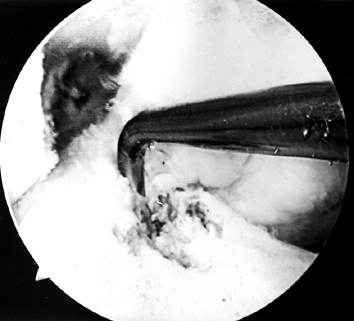

true posterior outlet (Fig. 89.8).

Figure 89.8.

Arthroscopic view of a right knee. The 5.5 mm round burr is just

“over-the-top” position. -

When the ridge is identified, place the

burr posterior to the ridge and move it from a posterior to anterior

direction to smooth the ridge. Use a curet to remove soft tissue from

the posterior outlet, and then hook a probe over the posterior edge to

confirm proper “over-the-top” positioning (Fig. 89.9).